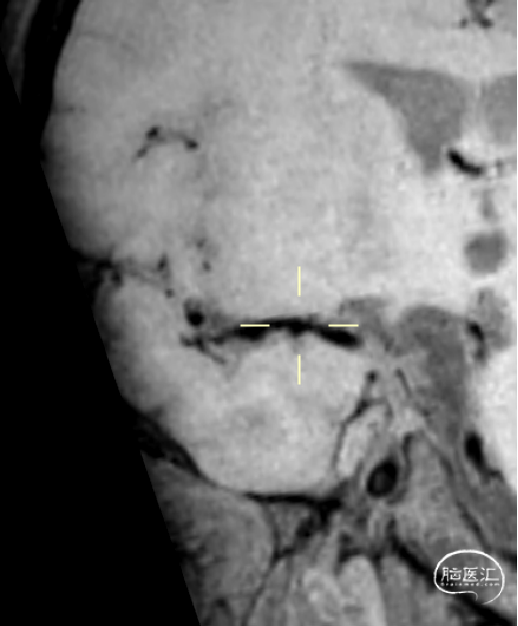

HRMR: